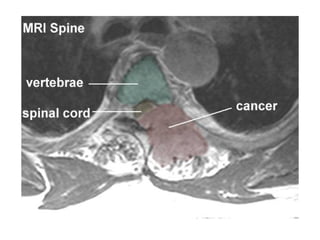

Compression of the spinal cord is due

predominantly to extradural metastases

(95%) and usually results from tumor

involvement of the vertebral column. A

tumor may occasionally metastasize to

the epidural space without bony

involvement.